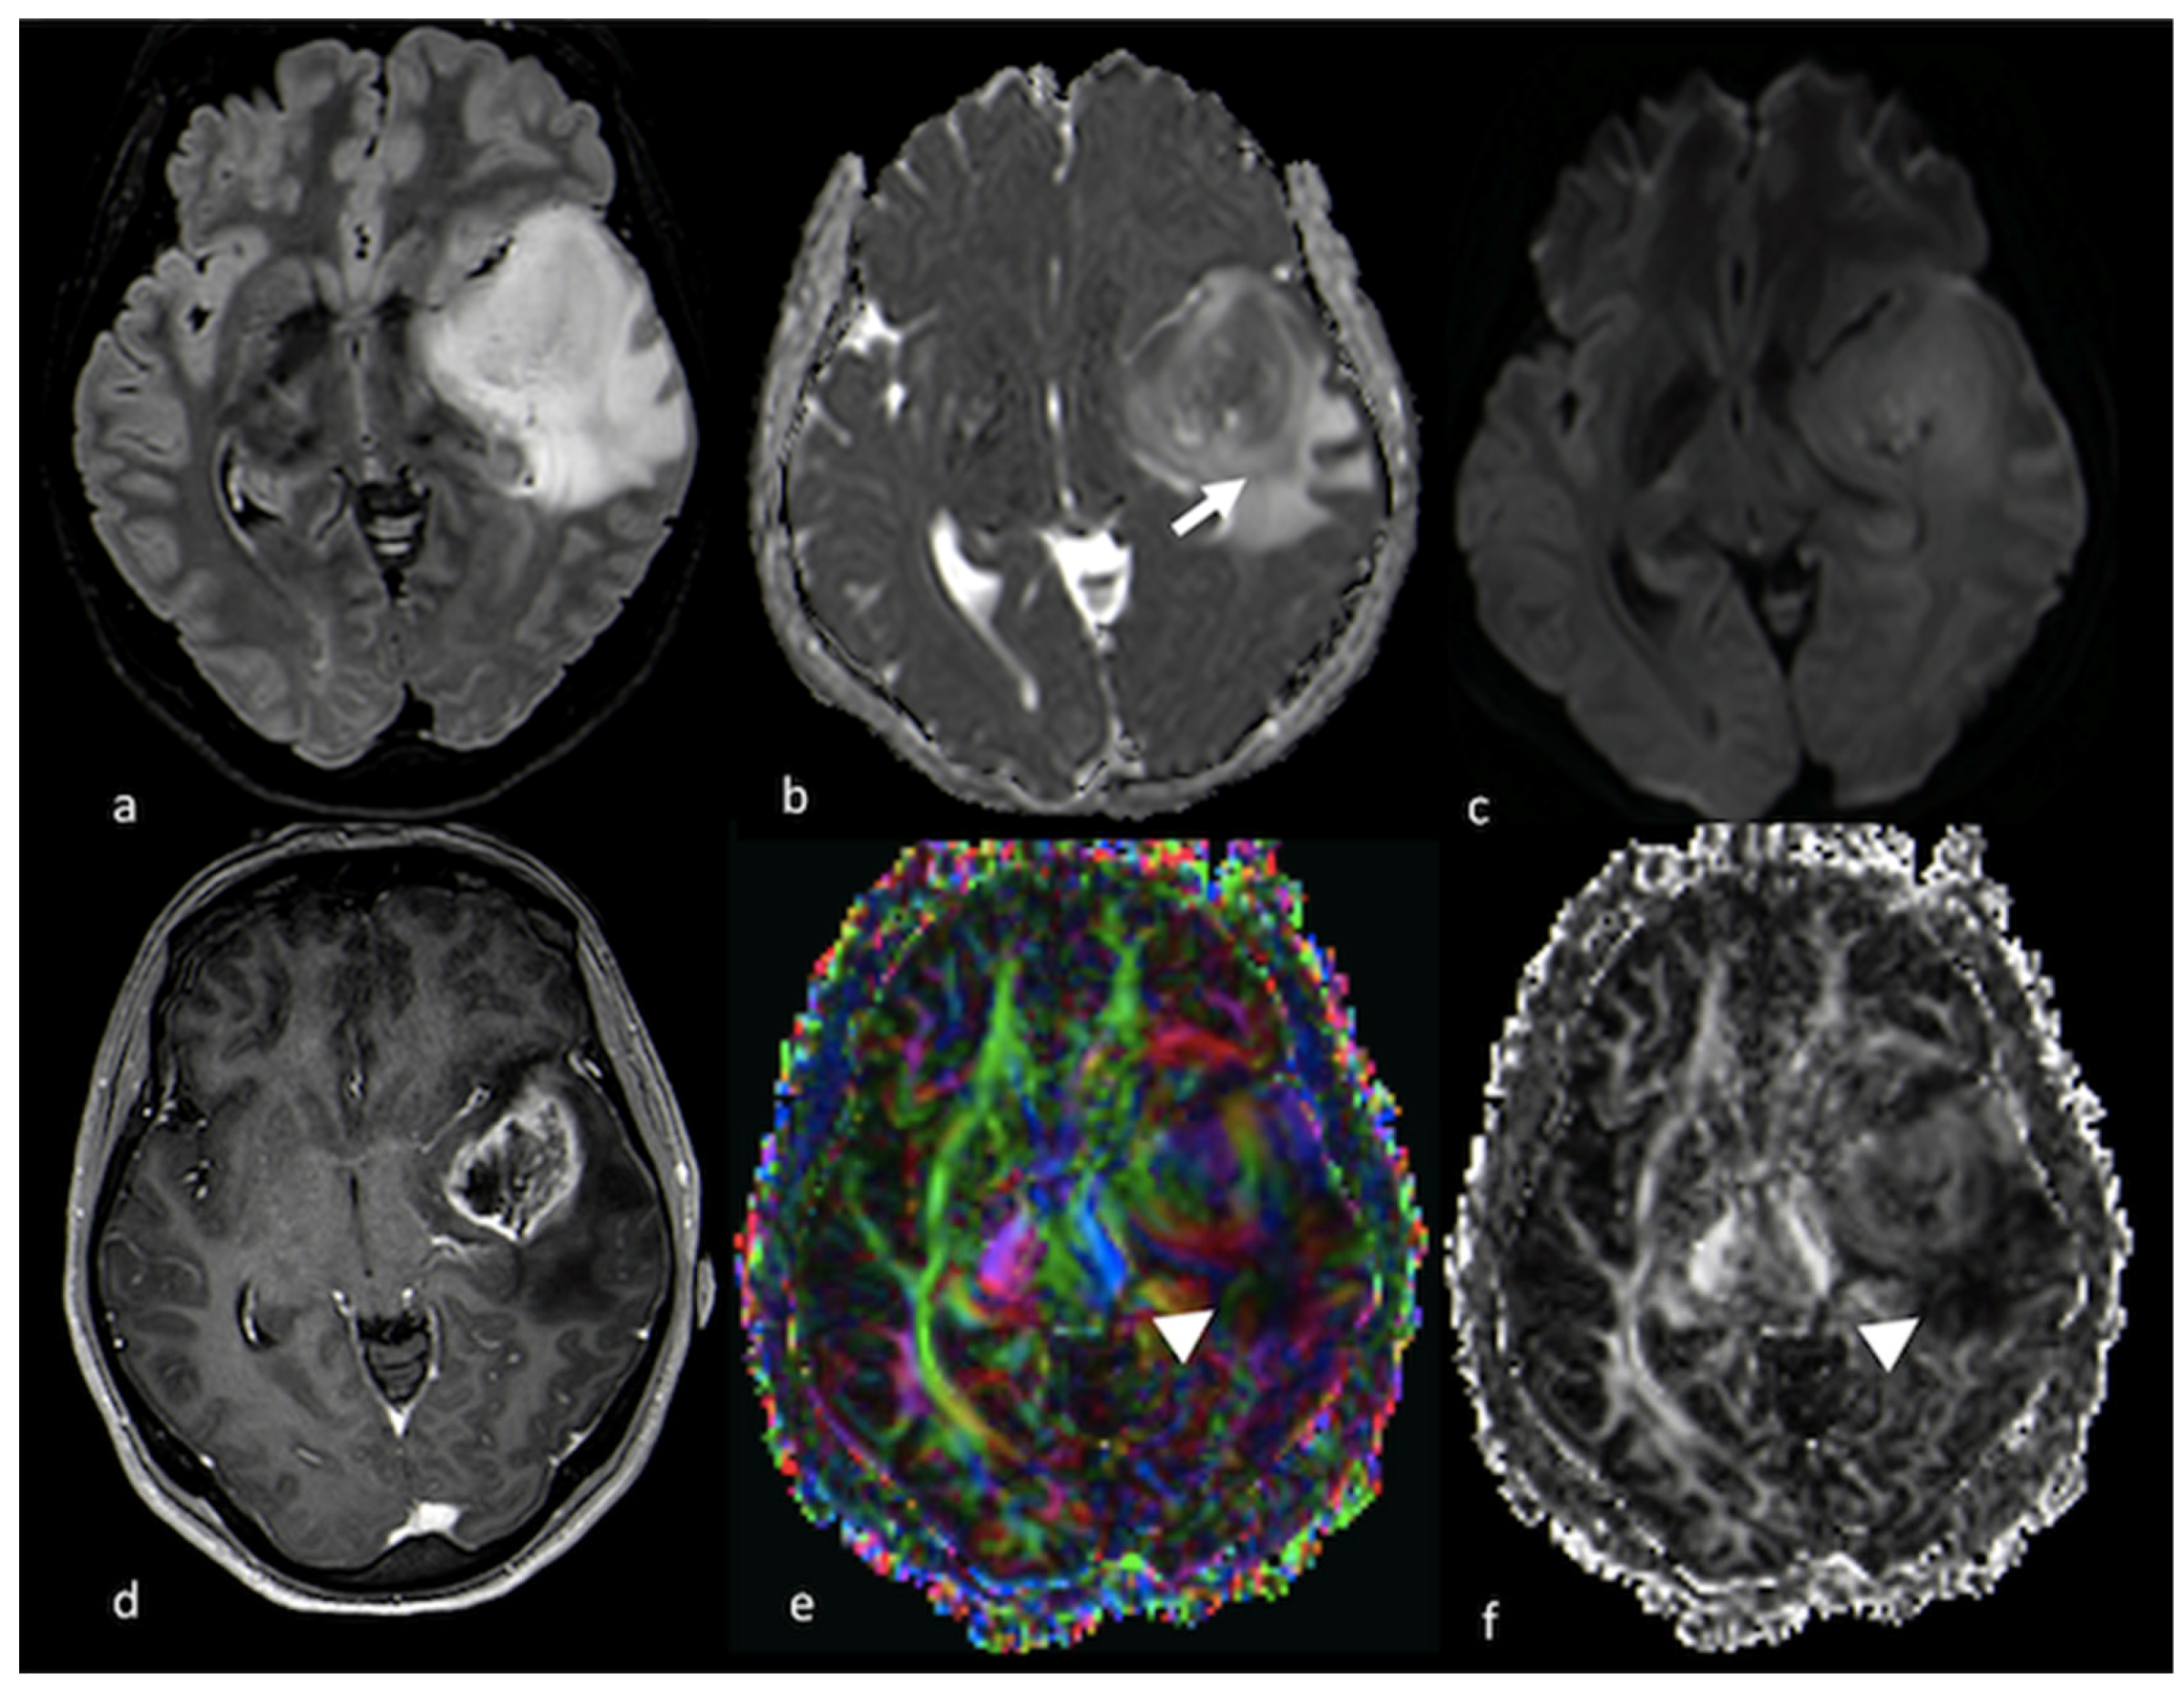

3.2.2. Diffusion Tensor Imaging (DTI)

3.2.3. Diffusion Kurtosis Imaging (DKI)